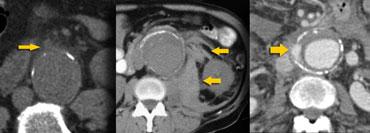

Các dấu hiệu chính của vỡ phình động mạch chủ bụng (AAA) bao gồm: thâm nhiễm mỡ quanh động mạch chủ, tụ máu sau phúc mạc và thoát thuốc cản quang tiêm tĩnh mạch.

TRÁI: Thâm nhiễm mỡ quanh động mạch chủ mức độ nhẹ, GIỮA: Xuất huyết vào khoang cạnh thận sau và quanh thận, PHẢI: Thoát thuốc cản quang tiêm tĩnh mạch

Bên trái là hình ảnh của ba bệnh nhân bị vỡ phình động mạch chủ.

Trong hình ảnh ngoài cùng bên trái, chúng ta chỉ thấy một ít mô mềm tỷ trọng cao ở ngoại vi tiếp giáp với túi phình, và đây thực sự là dấu hiệu cho thấy bệnh nhân có nguy cơ vỡ hoàn toàn.

Hai trường hợp còn lại cho thấy tụ máu sau phúc mạc và thoát thuốc cản quang ra ngoài động mạch chủ, giúp chẩn đoán dễ dàng hơn.